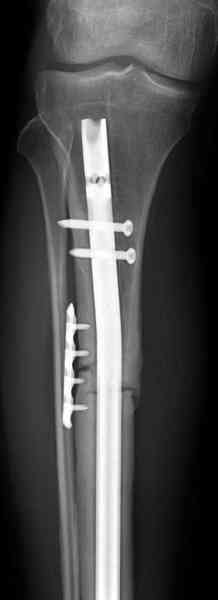

Оперирован в военном госпитале с заменой сегмента

аллокостью большеберцовой кости и после демобилизации явился для постоянного наблюдения по месту жительства.

Наши имели проблему со сращением, пришлось им сделать динамизацию, дополнительную аутопластику.

Снимки представлены.